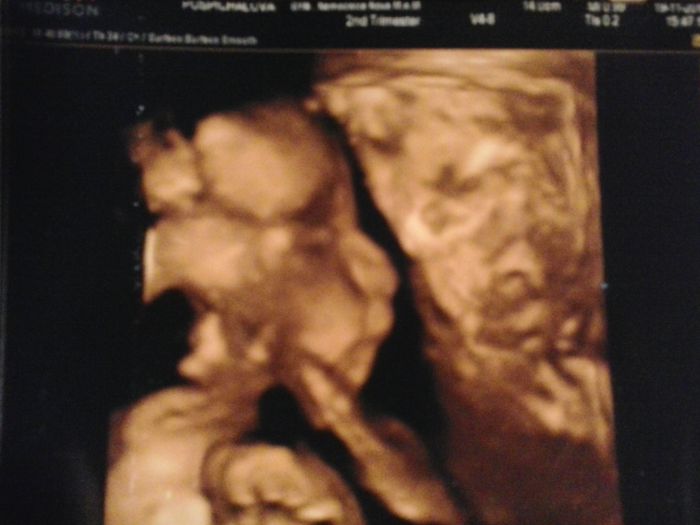

Ahoj holky tak jsme taky dneska byli u doktora na 3D UTZ a bylo to boží.Sice máme jen jednu dobrou fotku ale aspoň něco.Ležela jsem tam skoro půl hodiny a prcek ce pořád schovával pod ručičkou nebo pupečníkem

Jinak je to 100%kluk což se mi dost ulevilo, už kvůli tomu že mám doma mraky oblečení pro kluka

A poprvé ho doktorka změřila a zvážila takže já jsem dneska úplně šťastná